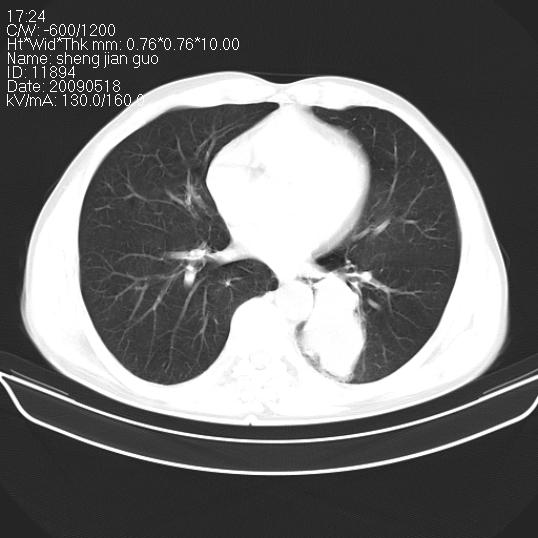

以下是引用zjzjr在2009-5-19 17:25:00的发言:[br]支持楼主考虑,另左肺下叶阻塞性炎症。

以下是引用zhao_bin2008在2009-5-19 17:48:00的发言:[br]支持左肺下叶周围型肺癌并阻塞性肺炎。

以下是引用杀毒软件在2009-5-19 17:36:00的发言:[br]支持楼主

以下是引用zsl6918在2009-5-20 7:10:00的发言:[br]左侧中心型肺癌!